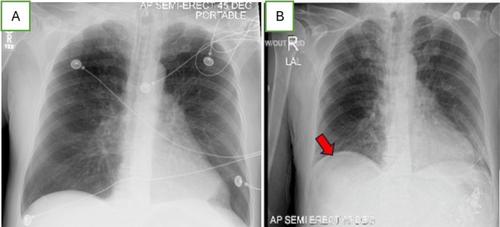

Gastric perforation is a serious yet rare complication in critically ill patients on mechanical ventilation and GI prophylaxis. This report highlights an unexpected gastric perforation in a patient with a negative barium swallow study while receiving GI prophylaxis during intubation. A 65-year-old male with COPD and tobacco use disorder was treated with Oseltamivir for Influenza A infection, intubated for acute respiratory failure, and received IV pantoprazole for GI prophylaxis. After extubation and an unremarkable barium swallow study, he developed abdominal pain and tachycardia. Imaging showed free air under the diaphragm, and a CT scan indicated gastrointestinal perforation. Emergency surgery confirmed an anterior gastric ulcer perforation with purulent peritonitis. He was successfully treated with a washout and antibiotics and was discharged in stable condition. This case underscores the necessity of vigilance for abdominal symptoms and the potential for gastric perforation in critically ill patients despite GI prophylaxis, highlighting the importance of recognizing early signs of pneumoperitoneum.